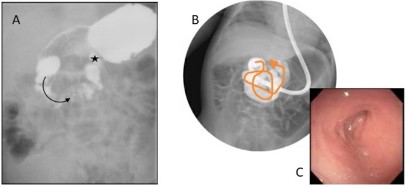

The most common finding documented on EF was a dilated duodenum just proximal to an area of luminal narrowing with associated caliber change (12/14 patients: 85.7%). Another 42.9% of patients (6/14) were found to have a “zig-zagging”, redundant, or tortuous duodenum (Figure 1). The differential diagnoses following EF included rotational abnormalities and partially obstructing Ladd’s bands, as well as possible annular pancreas or duodenal web. All patients were referred to general surgery for consideration of operative exploration and possible Ladd procedure. The study population included those patients that underwent a Ladd procedure for an intraoperative diagnosis of abnormal intestinal rotation with partially obstructing Ladd’s bands. One patient had a gastrostomy tube placed during the index operation as well.

Figure 1: Comparison of findings on UGI (A) and EF (B, C) for a single patient. A) The black arrow demonstrates the “C” loop of the proximal duodenum, and the black star highlights the location of the Duodenojejunal Junction (DJJ). This UGI study was reported as normal rotation due to the DJJ rising to the level of the pylorus and crossing to the left of the spine. B) EF demonstrated duodenal redundancy and hairpin turns (orange arrow) which were not appreciated on UGI. C) An endoscopic image demonstrating a duodenal hairpin turn that was difficult to traverse with the endoscope.